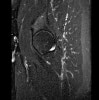

- Sagittal section

Sagittal PD fat suppression is sensitive to fluid that may be present with AVN or stress fractures.